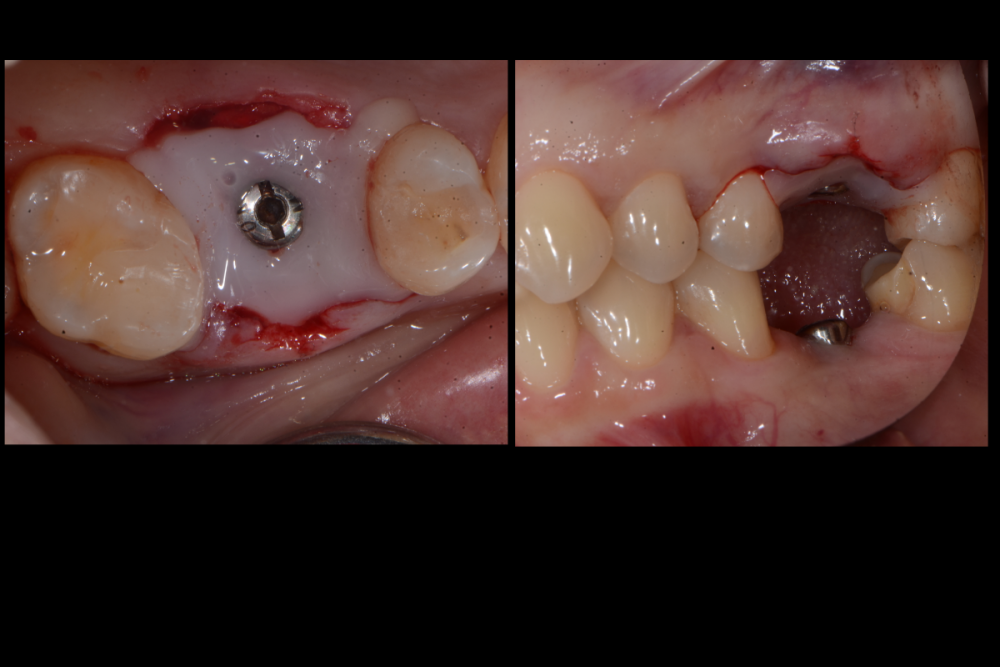

Карен Аванесов Опубликовано 10 ноября, 2021 Автор Поделиться Опубликовано 10 ноября, 2021 Придерживаясь правил форума, второе сообщение содержащее фотоматериал выдержанно в лучших традициях русской словестности, без сквернословия и непонятных иностранных слов, без применения шовного материала, широких формирователей десневой манжеты, без мягкотканной и прочей аугментации (наращивание костей что то все же не звучит прилично)), а самое главное, время затраченное на всю операцию 60 минут (имплантаты на нижней челюсти установил по лазерной технологии, без разрезов, Лазер - сила!). Время ожидания до ортопедического этапа 3 месяца. 6 1 Ссылка на комментарий

Карен Аванесов Опубликовано 14 ноября, 2021 Автор Поделиться Опубликовано 14 ноября, 2021 13.11.2021 в 08:55, annda сказал: У инженера гиперболоид был, однако Не претендую на раскрытие секретов, видимо, что- то сакральное. Анна Анатольевна, в данном контексте, упоминание лазера, не более чем гипербола. Улыбайтесь чаще, Вам идет улыбка) 13.11.2021 в 20:19, Марья Моревна сказал: А что это такое кругленькое виднеется в лунке небного корня на самом левом из трех снимков над панорамой? А Вы Марья Моревна глазастенькая! Это воздушный пузырь, там две перфорации синуса, после удаления кисты. Ссылка на комментарий

Карен Аванесов Опубликовано 14 ноября, 2021 Автор Поделиться Опубликовано 14 ноября, 2021 (изменено) 13.11.2021 в 20:19, Марья Моревна сказал: А что это такое кругленькое виднеется в лунке небного корня на самом левом из трех снимков над панорамой? Это некий цимус-изюминка, в этой работе Изменено 14 ноября, 2021 пользователем Карен Аванесов Ссылка на комментарий